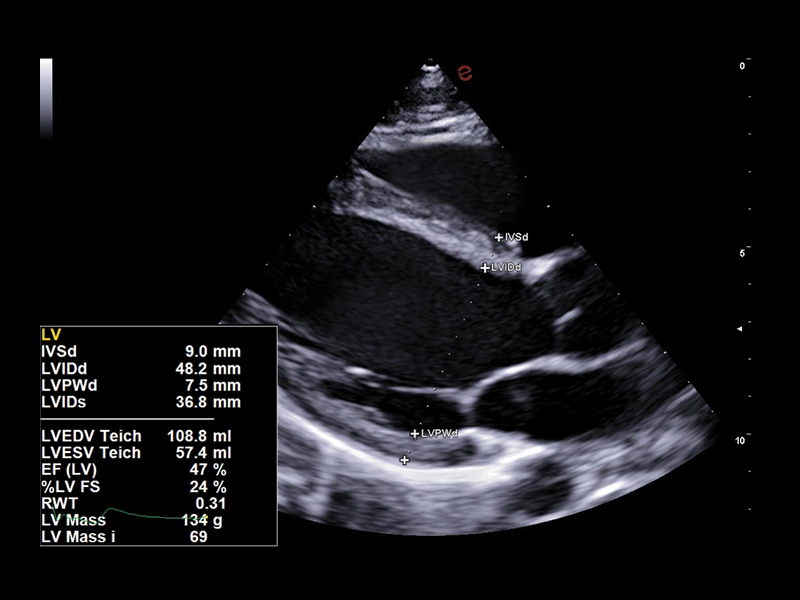

MyLab™E80 - AutoEF

MyLab™E80 - AutoEF

MyLab™Omega eXP - AutoEF

MyLab™Omega eXP - AutoEF

MyLab™X90 - AutoEF Automatic Ejection fraction assessment of the left ventricle

MyLab™X90 - AutoEF Automatic Ejection fraction assessment of the left ventricle

MyLab™X5 - AutoEF

MyLab™X5 - AutoEF

MyLab™X6 - AutoEF

MyLab™X6 - AutoEF

MyLab™X7 - AutoEF

MyLab™X7 - AutoEF

MyLab™Omega - Zero-Click AutoEF

MyLab™Omega - Zero-Click AutoEF

MyLab™A50 - AutoEF

MyLab™A50 - AutoEF

MyLab™A70 - AutoEF

MyLab™A70 - AutoEF